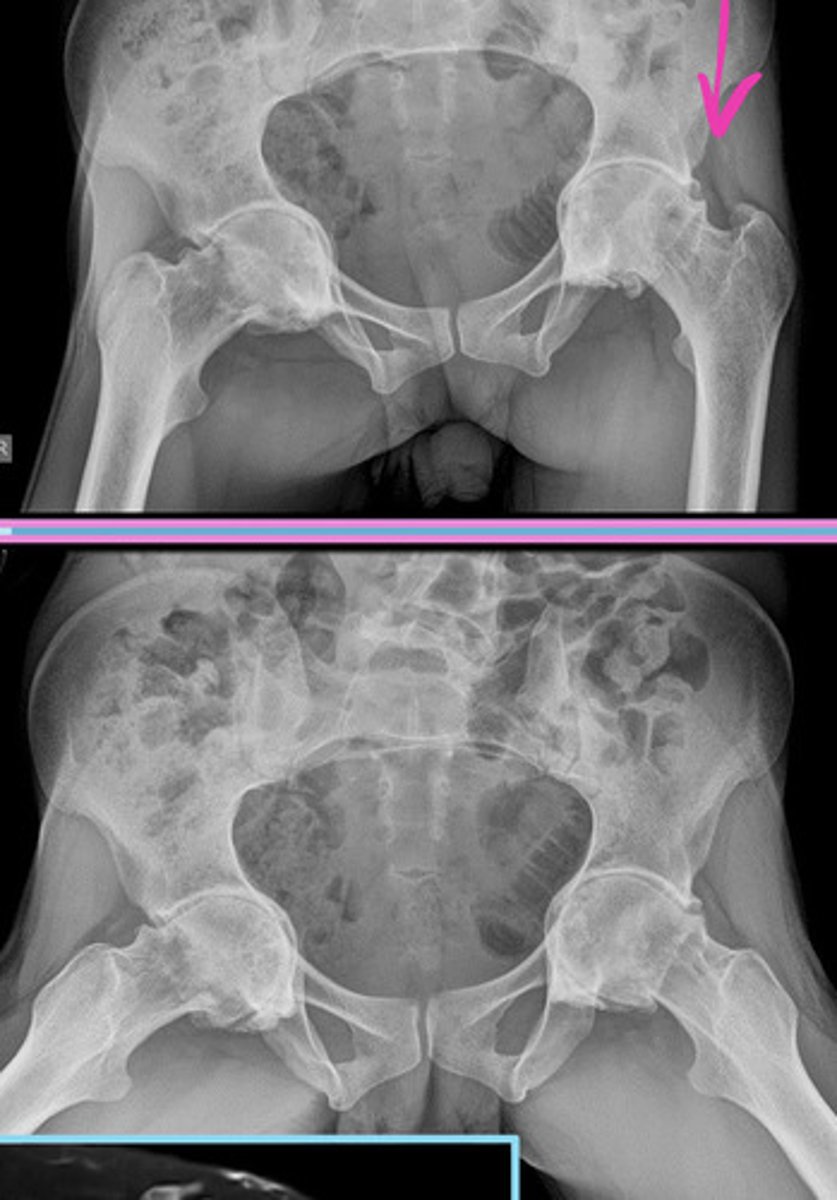

COMPLETE lumbarization vs sacralization

Complete lumbarization = 6 lumbar segments (S1 separated from sacrum)

Complete sacralization = only 4 lumbars (L5 fused with sacrum)

Image example of sacralization of L5